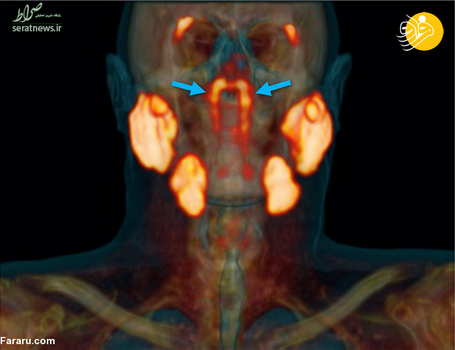

دانشمندان در موسسه سرطان هلند اعلام کردند که دو غده در جمجه سر، محل تقاطع حفره بینی و گلو، کشف کرده‌اند که احتمالا بخشی از سیستم غده‌های تولید کننده بزاق در بدن است. به گزارش فرارو، این محققان به طور اتفاقی هنگامی که برای درمان سرطان پروستات به اسکن غده‌های دیگر در بدن یک بیمار نگاه می‌کردند متوجه این دو غده شده‌اند. ‌ آنها سپس به اسکن 100 بیمار دیگر که سرطان پروستات داشتند نگاه کردند و وجود این دو غده را در بدن آنها هم تایید کردند. با این‌ حال پژوهشگران دیگر معتقدند این تحقیق تنها بر موارد محدودی بوده است که همه مرد و مبتلا به سرطان پروستات بوده‌اند و برای قطعیت وجود این دو غده باید بر روی بدن زن‌ها و شمار بیشتری از انسان‌ها هم تحقیق شود.